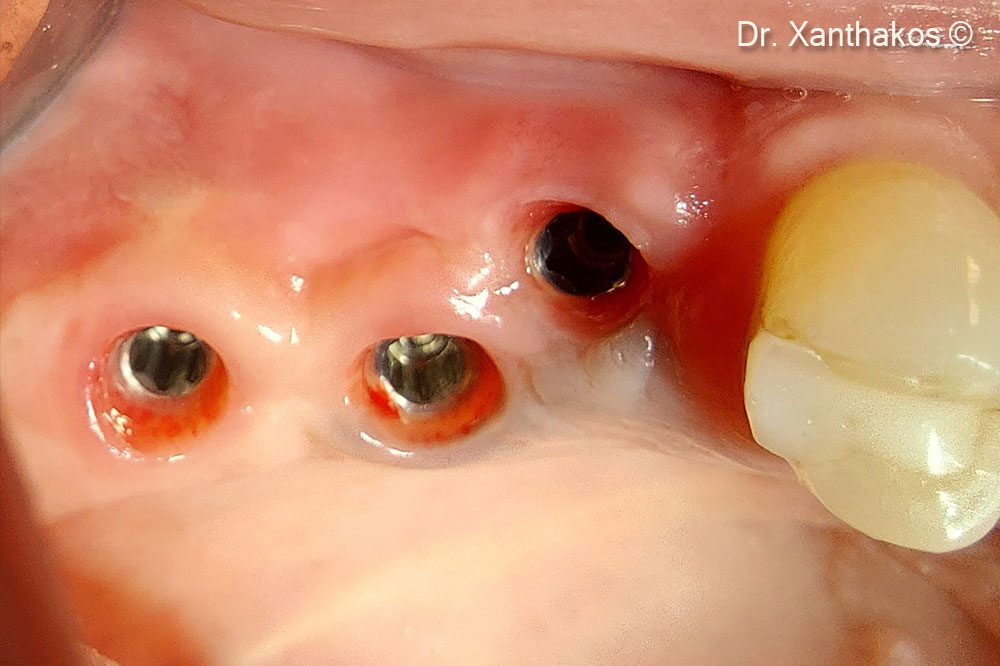

Immediate (after extraction of molars 16,17) placement of two blue sky implants in the position of the palatal roots

The two implants  were placed almost 2 or 3mm deeper to the residual palatal bony wall